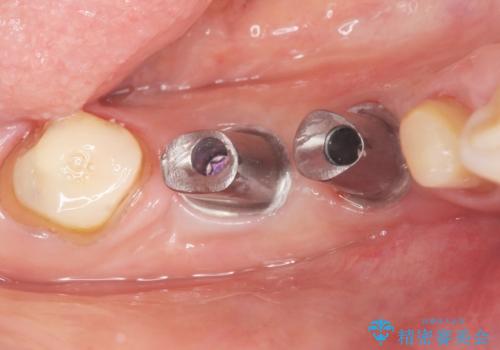

保存不可能な歯を抜去後、インプラント治療と根管治療を行いました。

- ¥1,177,000 (根管治療、土台、骨増生、インプラント・アバットメント×2本、仮歯・クラウン×3本) ※税込費用は治療当時の料金となります